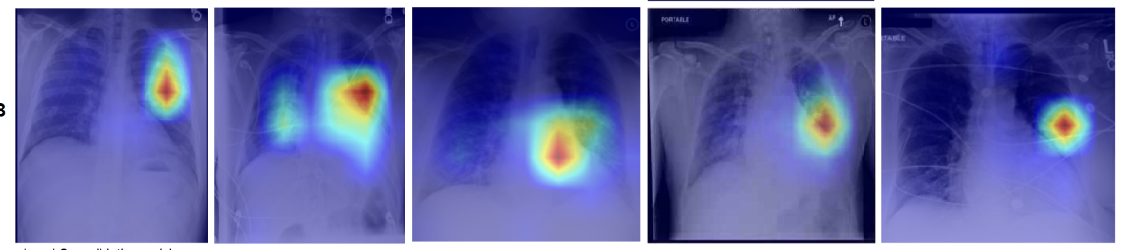

We propose MATEX (Multi-scale Attention and Text-guided Explainability), a novel framework designed to bridge this gap. MATEX generates anatomically faithful and text-aware attribution maps by leveraging three core innovations: (1) a multi-scale attention rollout strategy to capture signal flow across transformer layers, (2) clinically informed spatial priors derived from radiological text, and (3) a layer consistency mechanism to filter out unstable gradients. In this sense, MATEX serves as an interpretability framework for large vision–language models in medical imaging, analogous to the role of M2IB in explaining multimodal reasoning. As shown in Figure 1, MATEX provides joint visual–textual explanations by localizing lung cancer regions through anatomically consistent heatmaps while simultaneously highlighting the caption keywords that guide these attributions. This alignment between image evidence and clinical language enables transparent inspection of LVLM decision-making, closely reflecting radiologist-style reasoning and facilitating trustworthy deployment in medical settings.

Figure 3 shows a qualitative comparison between MATEX and M2IB on the MS-CXR dataset. Each column depicts a clinical case, with MATEX heatmaps on the top row and M2IB results below, visualized as overlayed attribution maps on chest X-rays.

Figure 3 illustrates that MATEX offers several consistent improvements over M2IB. Across all evaluated cases, MATEX produces heatmaps with sharper localization and tighter alignment to pathological regions, enhancing anatomical coherence. In scenarios involving bilateral or multi-zone findings—such as lower lobe consolidation—MATEX accurately captures both affected zones while avoiding overspill, whereas M2IB often yields diffuse attention. Additionally, MATEX exhibits improved boundary adherence, particularly in cases of opacification, which enhances interpretability for clinical use. It also demonstrates reduced noise activation by limiting attribution to relevant structures, unlike M2IB, which sometimes highlights unrelated areas.

These improvements are attributable to MATEX’s ability to produce more anatomically precise and clinically aligned explanations. The framework effectively captures multi-region pathologies without spatial drift and maintains clear boundaries around relevant findings.